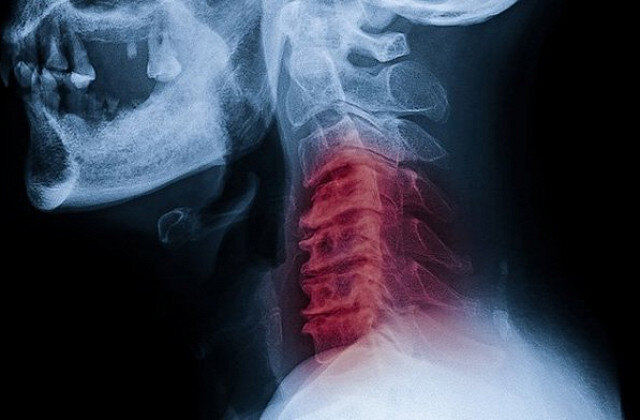

Парень попал в больницу с инсультом, хрустнув шеей

Это был инсульт, вызванный разрывом позвоночной артерии, которая снабжает мозг кислородом. Хейдер сначала защемил сосуд, а потом, сам того не ведая, резким силовым движением разорвал его. Мозг перестал получать достаточно кислорода, что и привело к утрате некоторых функций. Хейдеру очень повезло, что врачи в больнице оказались готовы к подобной неожиданности — его спасли буквально за 10-12 минут до фатального исхода.

Сегодня, спустя несколько месяцев, Джош Хейдер может самостоятельно передвигаться, он не утратил интеллектуальных способностей, лишь жалуется на «непослушную» левую руку. И, разумеется, строго настрого зарекся разминать шею. По словам нейрохирурга Казума Накагава, это чудо, что молодой мужчина выжил. Разрыв позвоночной артерии — недуг молодых и активных, но пока у врачей слишком мало информации для того, чтобы научится его предотвращать.

Накагава отмечает всего несколько явных случаев в своей практике. Можно сказать, что 99% людей вне зоны риска, но что именно делает 1% оставшихся уязвимым к повреждениям позвоночной артерии, ученые пока понять не могут. Одно им известно точно, если у вас есть такая предрасположенность, то даже самая простая нагрузка на шею может стать фатальной.